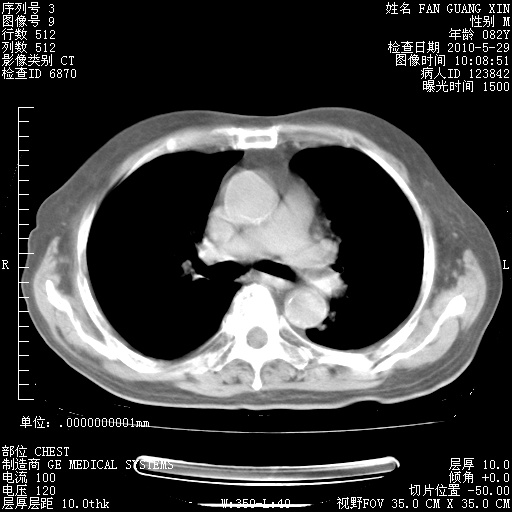

还需要哪些辅助检查?我们医院排除真菌感染没有任何检验方法,胸片好像能够排除肺部真菌感染。